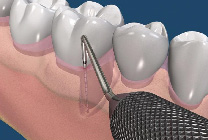

由於顯微鏡具有高倍率的放大效果,並提供卓越的強化光源,牙科的治療都相當微小,一般的放大鏡可放大約2-8 倍,而顯微鏡大約可放大約 30-40 倍,讓整個治療過程可以持續擁有清晰的視野,所以,顯微治療技術相較於傳統治療,最直接的突破即在於大大地提昇了醫師雙眼的透視能力,使得極細微的組織結構都能夠明顯的被呈現出來。因此,藉由這樣的特性,當顯微鏡被應用在根管治療上,便成為絕佳的利器,可以讓原本難以尋找的根管入口在顯微鏡下無所遁形,而原本錯綜複雜的根管系統也不再是一個讓人無法探索的區域。(圖01~03)

圖3